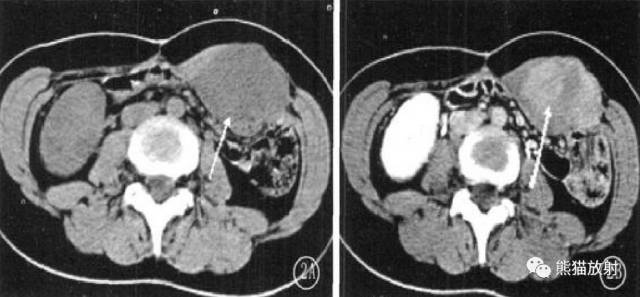

3、病灶边界多较清楚,也可浸润腹壁肌肉(筋膜尾征-较特征性表现)和皮下组织,或跨肌间隙,与腹膜、腹腔脏器粘连;

4、密度较均匀,很少见到坏死、钙化或者液化;

5、DTF信号特点及其不均匀性与病灶内组织学成分的比例和分布有关:细胞成分多的区域T2WI信号较高,胶原纤维多的区域T2WI信号较低;

6、病灶内各序列见条带状低信号影,无明显强化,病理为致密胶原纤维化和少细胞区,是 DTF较特征性的表现。